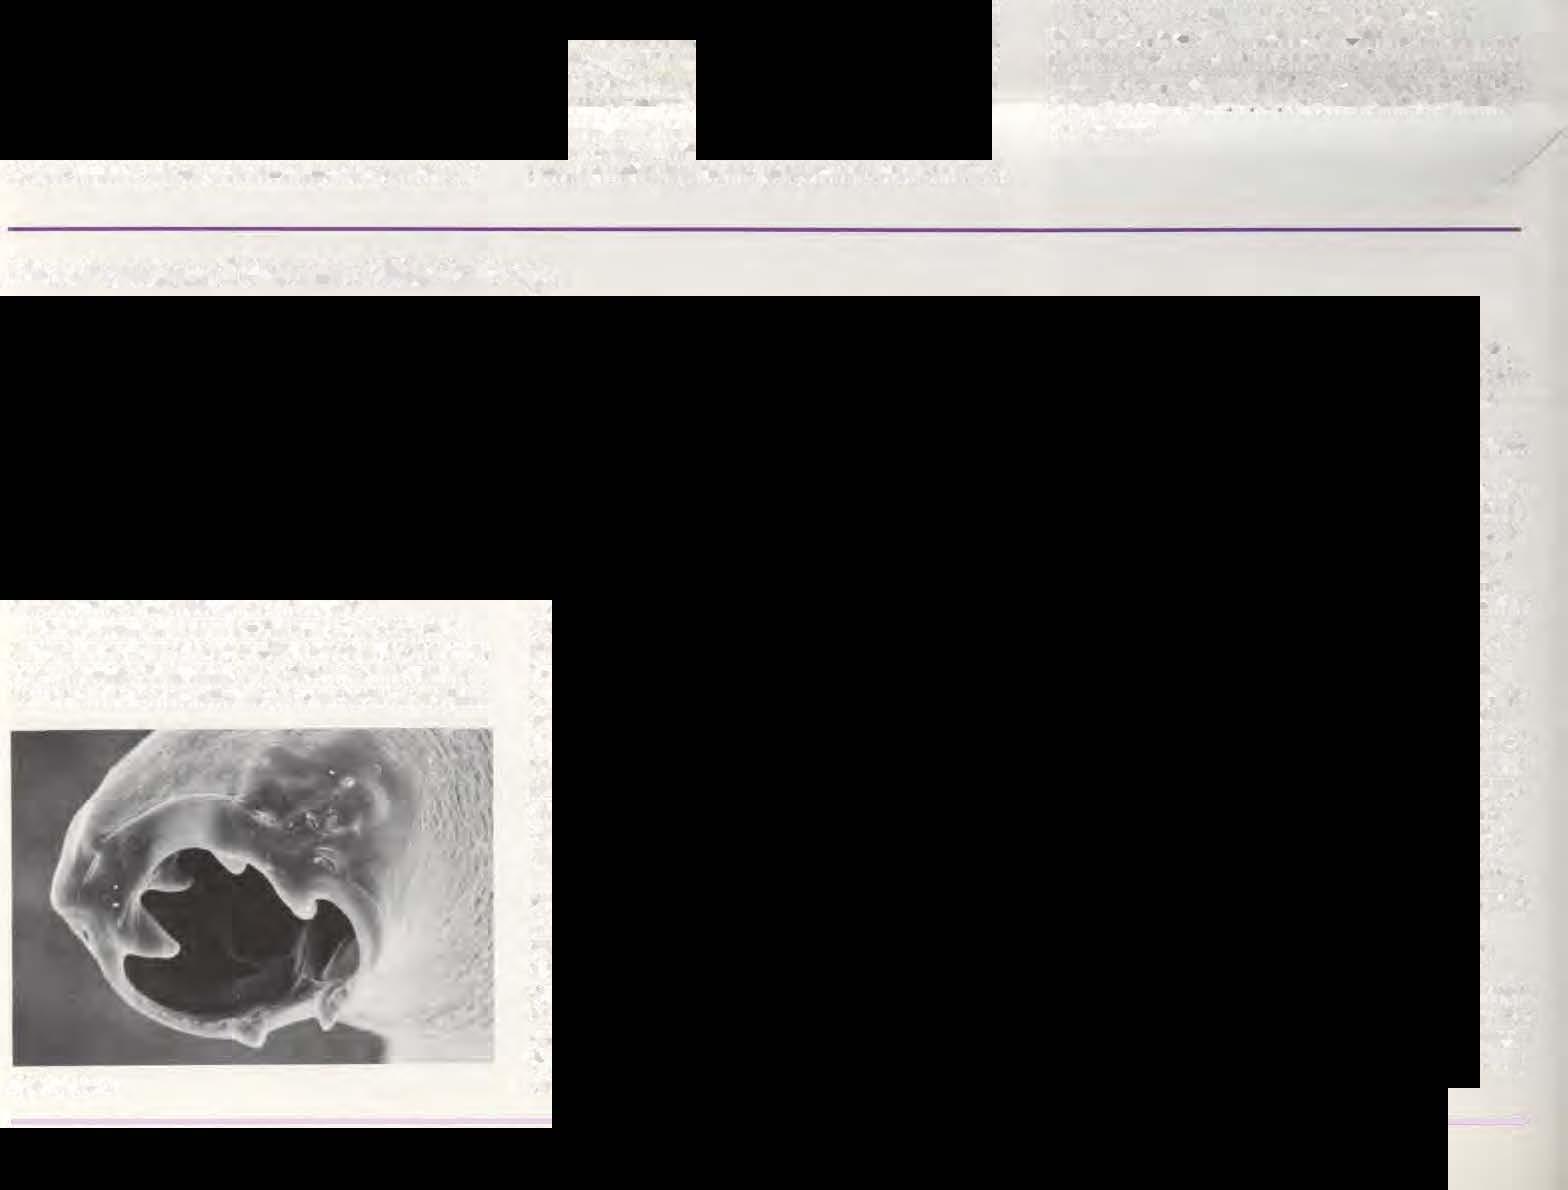

ChickenwithL.T.

Dr. Davison may be contacted when a new or serious disease is suspected. One disease that has recentlycaused ou1breaks in Pennsylvania as well as in other states is laryngotracheitis (lT) LT is a respiratory disease of chickens caused by a herpes Vlrus. Pennsylvania has experienced two severe outbreaks overthepastfouryears. In 1984-1985, 38 flocks consisting of approximately I.8 million chickens were affected with LT. Tn 1987-1988, 86 flocks consisting of over 5 million chickens have been confirmed with LT. The majority of affectedflocks were unvaccinatedbroilers,however, pullets, layers, breeders, roasters and backyard flocks were also diagnosed with LT.

Dr. Davison has coordinated the control program for LT in Pennsylvania andhas organized a network of producers whomeet with her to cliscuss the status of the LT outbreak. ''We now have 25-30 representatjves from various companies who meet and coordinate their vaccination program for LT." She keeps industry personnel informed about the current status of LT through a weekly newsletter.

Dr. Davison has done extensive research on LT. These include assessment of vaccination programs, rransmtssion studies and the role of maternal antibody protection. There are stiU many unanswered questions concerning LT. The Laboratory or Avian Medicine and Pathology will continue to do research on LT focusing on the characterization of field isolates using challenge work and restriction endonuclease stuclics.